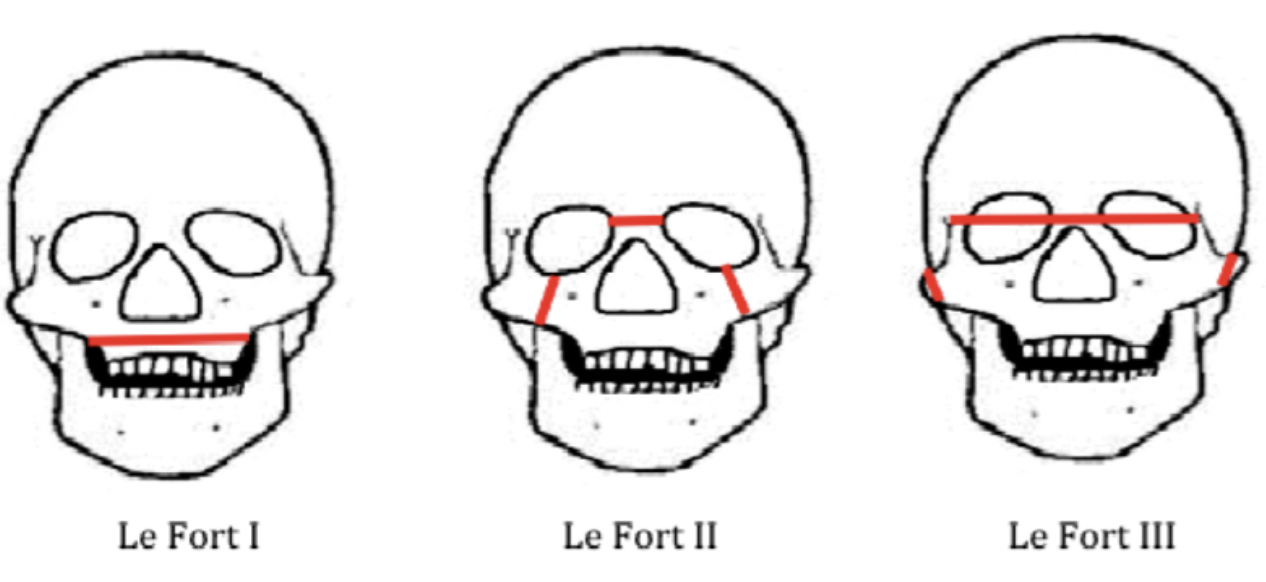

骨折